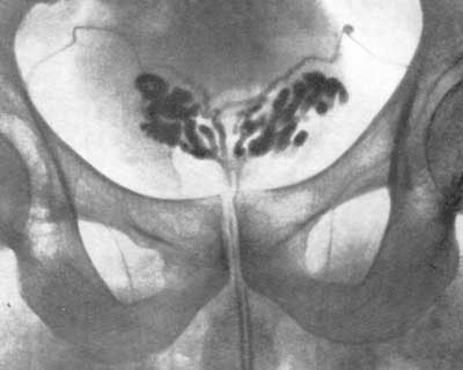

Третья ступень диагностики — инструментальные методы. Рекомендуется ультразвук семенных пузырьков и простаты, который может быть выполнен с использованием трансректального или абдоминального датчика. Трансректальный метод дает наиболее четкое изображение. В ходе УЗИ оценивают размеры и структуру пузырьков, а также наличие гнойных участков.

При хроническом везикулите в секрете часто обнаруживаются лейкоциты, эритроциты и неподвижных сперматозоиды. Бактериологическое исследование этого секрета помогает определить причину инфекции и выбор соответствующего антибактериального средства. Ультразвуковое обследование может показать, что семенные пузырьки расширены и деформированы.